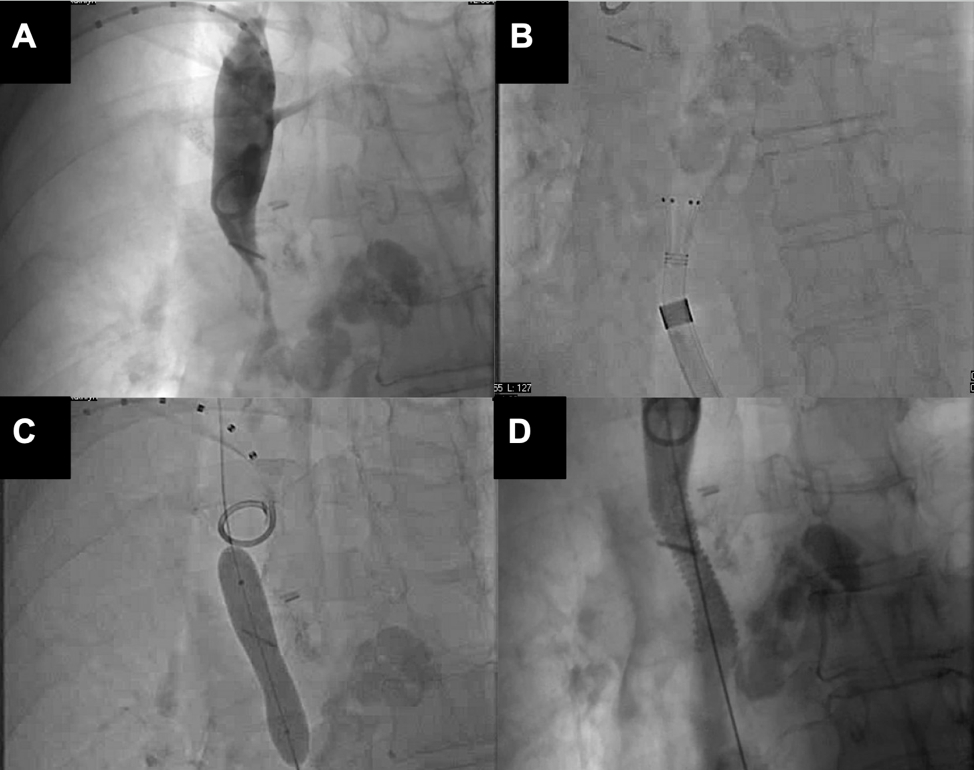

A 64 year-old-female with history of cerebrovascular accident on Eliquis, right upper lobe squamous cell carcinoma of the lung in remission, and a mediastinal nodule under surveillance presented with facial and bilateral upper extremity edema. CT revealed bilateral pulmonary embolism and a large SVC thrombus causing impaired venous return. Invasive angiogram confirmed a 95% thrombotic tubular stenosis for which she underwent aspiration thrombectomy with alpha VAC F-18, then angioplasty with an Armada (Abbott) 10 x 40 mm compliant balloon and stenting with the Express (Boston Scientific) 10 x 37 mm stent. There was 0% residual stenosis and immediate clinical improvement. Oncological workup confirmed the right mediastinal mass to be a recurrence of squamous cell carcinoma.

SVC syndrome occurred due to mediastinal mass compression and a near occlusive SVC thrombus. Aspiration thrombectomy was effective in treating the SVC thrombosis and was performed alongside pulmonary embolism thrombectomy. The Armada balloon is intended for lesion dilation in the peripheral arteries, but was safely used here for venous dilation. The Express stent is intended for palliation of malignant biliary neoplasms but has versatility and was utilized here for malignant neoplasm surrounding the SVC. Peripheral endovascular stenting is an advantageous treatment option for malignant SVC syndrome given the challenges due to recurrence from mass effect. This provides additional support to maintain vessel patency and is a safe palliation option for improvement in quality of life.